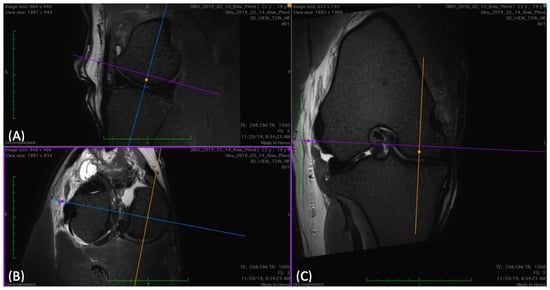

Figure 5. (A) Sagittal, (B) transverse, and (C) dorsal view of 3D T2-weighted view images of a stifle, where the plane for the regions of interest (ROIs) is determined for the medial femorotibial joint. To have a sagittal view directly through the middle of each condyle, the dorsal plane (blue) was aligned in parallel to the caudal horn of the meniscus and the transverse (purple) parallel to the joint space. In the dorsal (C) and transverse (B) views, the sagittal plane (yellow) was placed through the center of the condyle. This was repeated for lateral measurements.